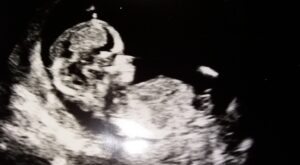

Sera positiva ayudaaa

Non classé

hay 9 años